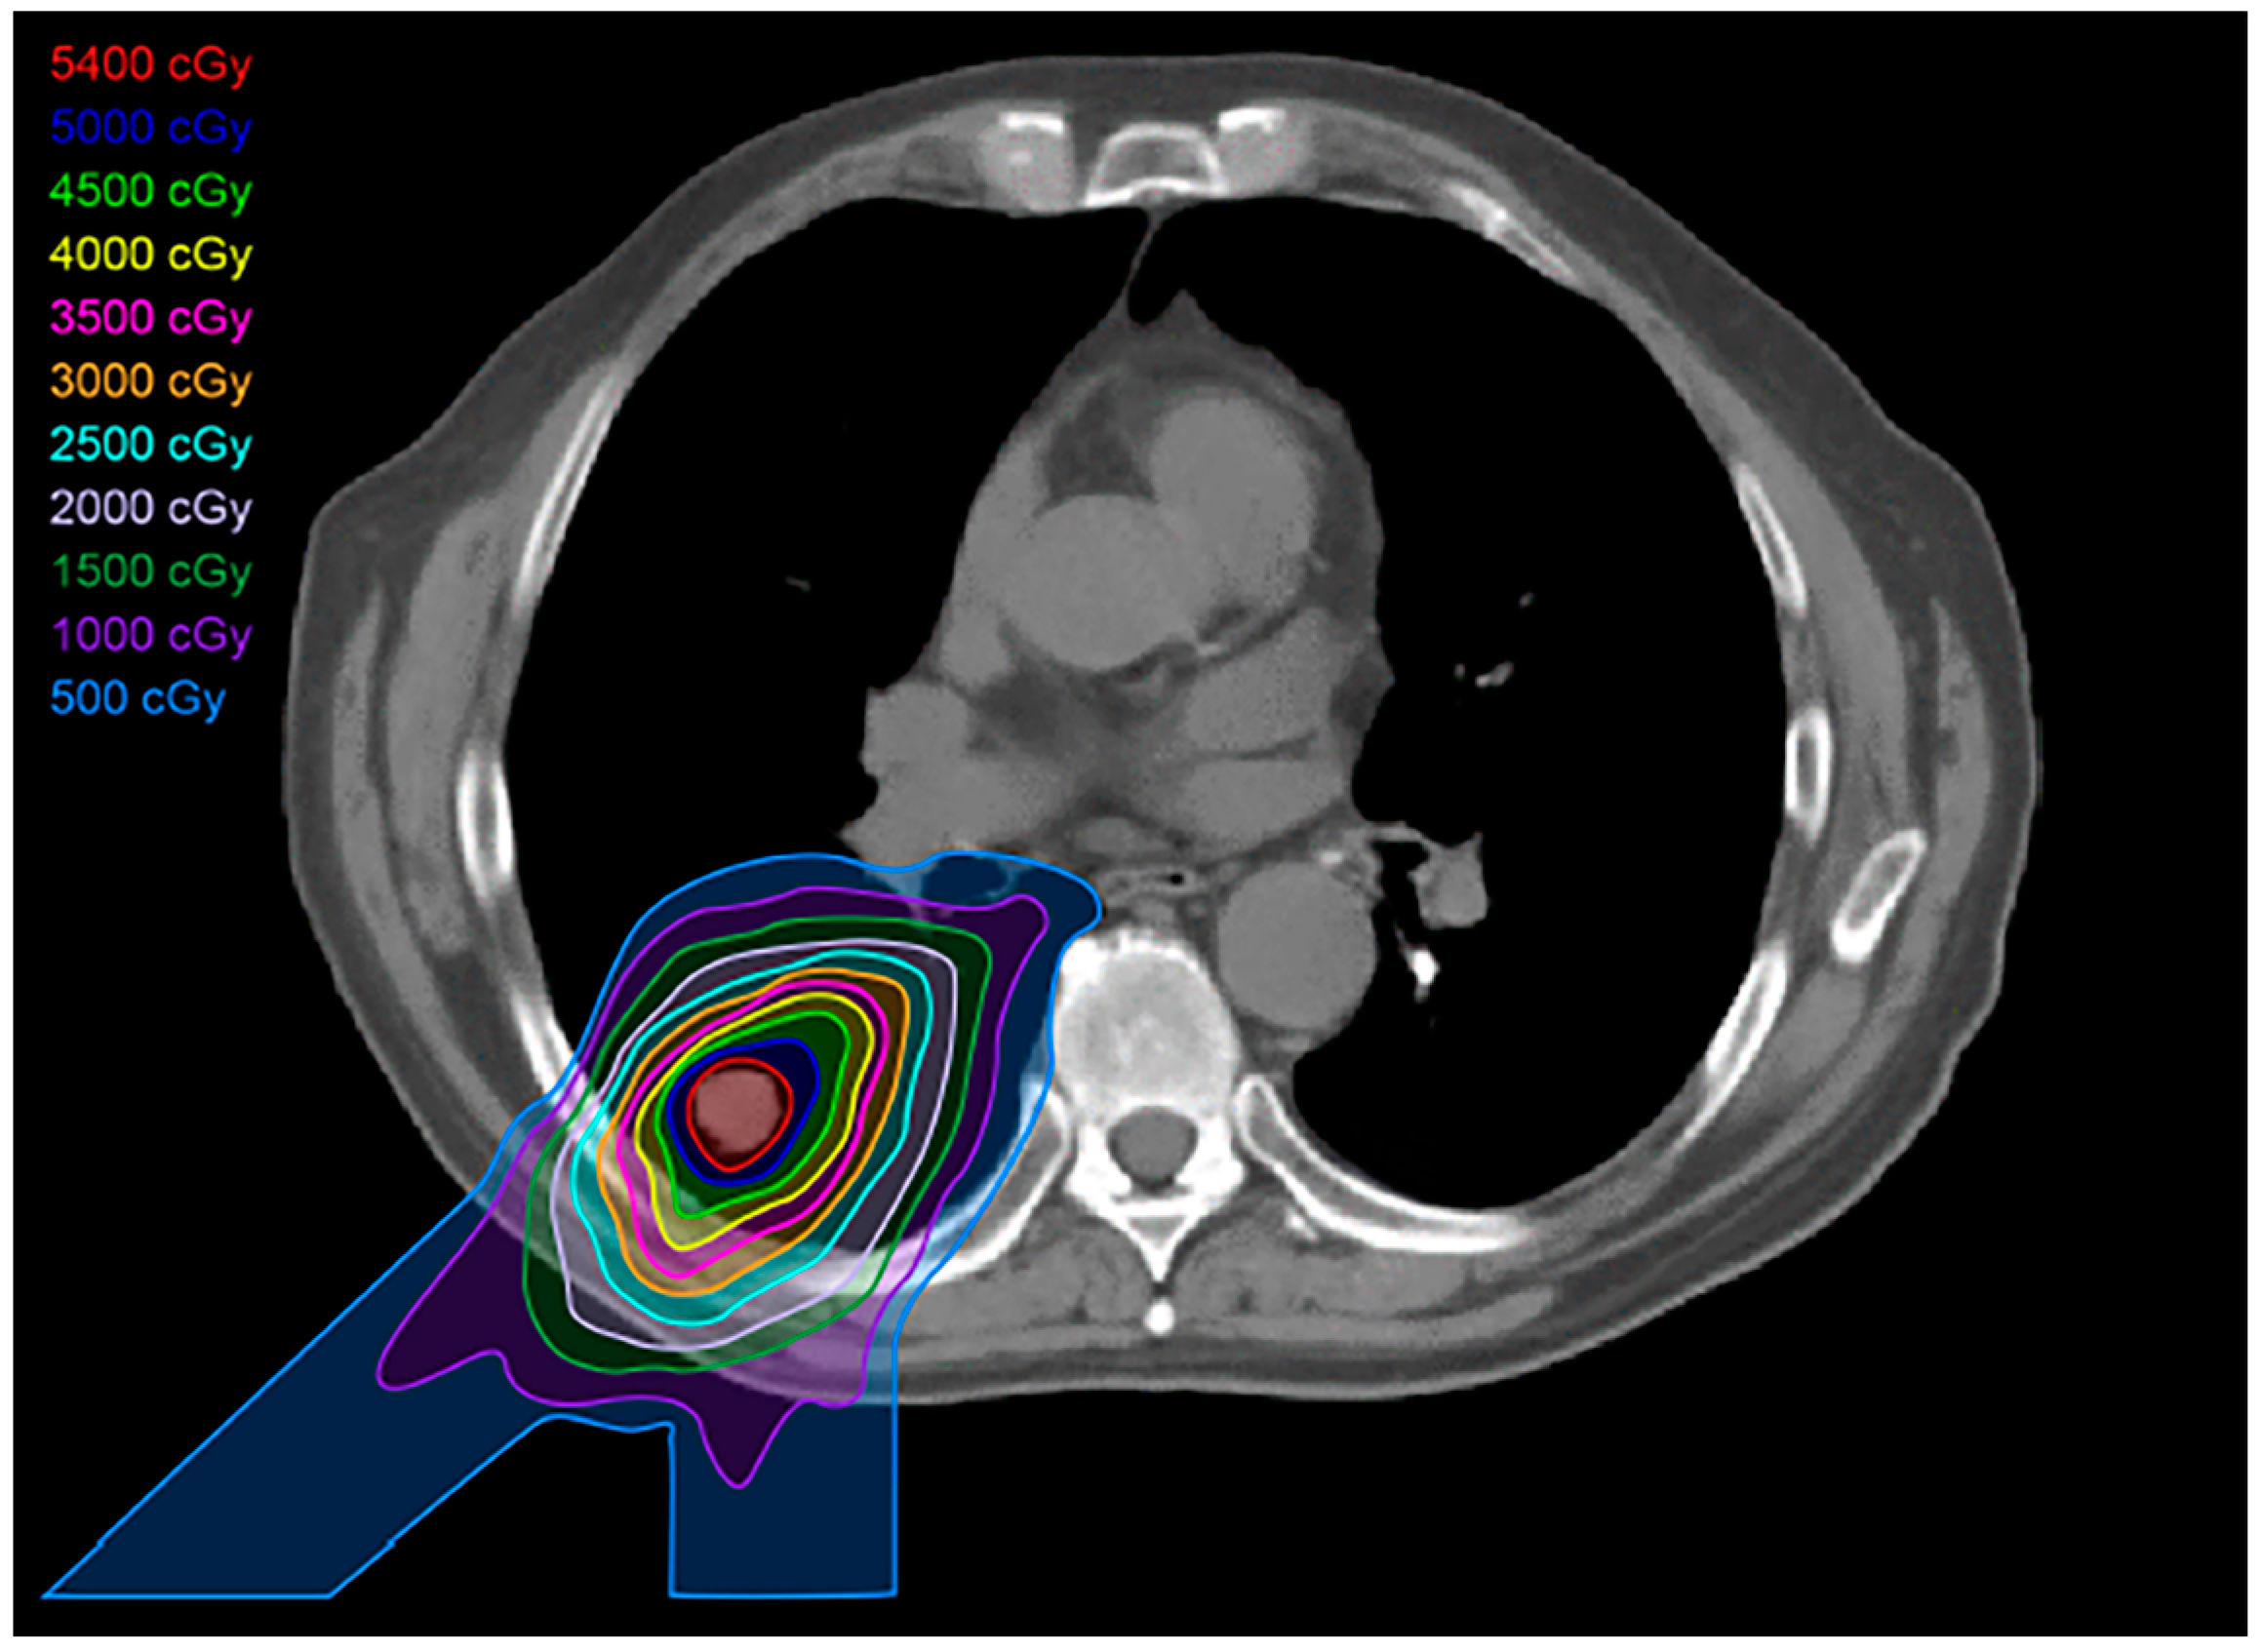

2.6. Proton Therapy